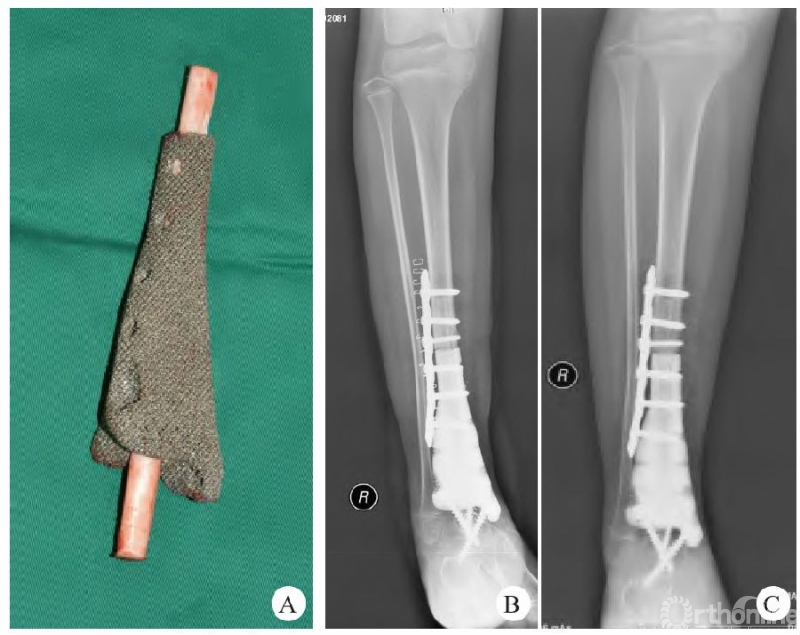

四川大学华西医院团队[4]应用3D打印髌骨假体治疗复发性髌骨骨巨细胞瘤,术后患侧膝关节主动屈曲角度由(22.50±6.45)°~(76.25±4.79)°提升至0~(112.50±9.57)°;肌力强度由(2.75±0.50)级提升至(5.00±0.00)级;骨与软组织肿瘤协会(MSTS)评分由(12.25±1.71)分提升至(27.25±1.71)分,在治疗髌骨骨巨细胞瘤的术后早期疗效显著。